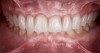

Fig 21. Postoperative frontal intraoral view in maximum intercuspation with full-contour high-translucent zirconia restorations.

Figure 21

Fig 22. Postoperative extraoral view of patient’s smile.

Figure 22

A 40-year-old patient presented with the chief complaint: “My teeth are cracking, and I would like to have my original bite.” Dental findings included Class I occlusion with slight misalignment between teeth Nos. 8 and 9. Generalized severe occlusal wear and slight Class I mobility of teeth Nos. 23 to 26 were noted. Caries lesions were found on teeth Nos. 2, 4, 6, 8, 9, and 14 and abfraction lesions on teeth Nos. 4, 5, 10, 11, 13, 20, and 21. Figure 1 through Figure 3 depict the preoperative situation. Full-mouth rehabilitation was suggested. The goals for the restorative treatment were management of erosive etiology, conservation of tooth structure, and long-term protection of the restorations. A diagnostic wax-up was instrumental in determining functional and esthetic treatment goals and establishing new anterior guidance (Figure 4). A comprehensive, step-by-step treatment approach was applied, which, after periodontal pretreatment, caries control, and provisionalization, included definitive preparation (Figure 5) and restoration of the maxillary anterior teeth to establish anterior occlusal guidance. CAD/CAM–fabricated full-contour monolithic high-translucent zirconia crowns (Katana™ UTML Ultra Translucent Multi-Layered, Kuraray Noritake Dental, kuraraynoritake.com) were fabricated (Figure 6 and Figure 7) and cemented with self-adhesive resin cement (Panavia SA, Kuraray Noritake Dental). Figure 8 demonstrates the cemented anterior crowns and refined conservative preparations of posterior teeth, which were performed with minimal tooth-structure removal. High-translucent monolithic zirconia onlays and crowns were fabricated (Katana Zirconia UT, Kuraray Noritake Dental) (Figure 9 to Figure 12). The posterior restorations were adhesively bonded following the APC zirconia-bonding concept. APC-Step A involved air-particle abrasion with 50-μm aluminum oxide at 1.5 bar with a chairside microetcher (Figure 13), followed by application (APC-Step P, Figure 14) of a special ceramic primer (ClearfilTM Ceramic Primer, Kuraray Noritake) with adhesive phosophate monomers (MDP). Relative moisture and contamination control was achieved with cotton rolls and retraction cords. Rubber dam placement, which is always preferred, was difficult in this situation. The enamel surfaces of the abutment teeth were selectively etched (Figure 15) with 35% phosphoric acid (K-Etchant Gel, Kuraray Noritake Dental) and the dentin conditioned (Figure 16) with a self-etch dentin primer (Panavia V5 Tooth Primer, Kuraray Noritake Dental). A dual-cure adhesive resin (Panavia V5 Paste Universal, Kuraray Noritake Dental) was dispensed directly into the restorations with an automix syringe. The restorations were inserted, and excess cement was carefully removed (Figure 17 and Figure 18) before light polymerization (Figure 19). Postoperative views depict the treatment outcome (Figure 20 to Figure 22).